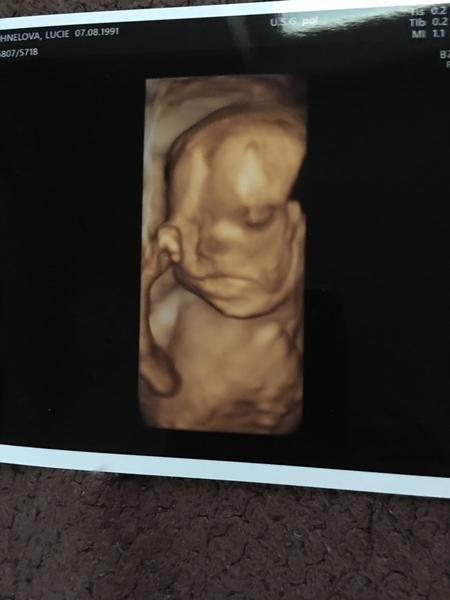

Ahojky, tak se hlásím po dlouhé době. Dnes 26+1 jsem byla na testech na těhotenskou cukrovku a dalo se to v klidu zvládnout ( zítra výsledky ... snad bude vše v pořádku). V 1 trimestru mne zlobil hematom, ve druhém pro změnu polyp, ale už to beru jako samozřejmost 🙂. Čekáme chlapečka. Už ho pěkně cítím já i manžel, i když mám placentu uloženou na přední straně. Asi dva dny zpět mne začala pálit žáha na kterou mi naštěstí zabírá Rennie. Výbavička se mi pomalu ale jistě kupí na balkóně ... už jen postýlka a vymalování ložnice chybí 🙂 🙂

@snazilka3 ahoj, to je paráda 😊 ja jsem dnes 23+0 a v 18tt jsem byla na plodovce, kde vyšlo naštěstí vsehcno v pořádku jen ma maly vadu jako já.. Je přenašeč a ma balancovanou aberaci... Asi týden po plodovce jsem byla v nemocnici, protože mam problémy s pupikem, které jsem měla už dříve, takže teď je to mnohem horší, jak všechno roste a roztahuje se, takže někdy umíram bolesti.. Musím si stále dávat pozor na každý pohyb, nesmím zatinat břicho, dělat prudké pohyby, předklanet se, a příště se pupiku nesmím ani dotknout, jinak mi to hned začne.. Nevím, co to jena ani doktoři.. Pry může být něco v břiše, jako třeba srusty nebo tak něco.. Takže nemůžu ani ns procházku, protože jdu kousek a uz to bolí, jsem z toho špatná, chteka jsem být v těhotenství aktivní a nemůžu. Takže mam strach z každého dne, jak mi poroste bříško, tak to bude určitě horší a horší, jenže když mi to začne, tak se ta bolest nedá vydržet ale prý se nic jiného dělat nedá.. Takže ani nevím, jak porodim, když nemůžu ani na wc tlačit.. Jinak jsou i jiné problémy 🤣 pálení záhy, hemeroidy, bolest zad a kyčli, bolavé a krvácení dásní, 7 kilo nahoře, velká a bolavá prsa.. Std atd.. Bych tu byla do zítra.. Takže sice jsem šťastná, ze čekám nase vymodlene miminko ale těhotenství si opravdu neužívám, uz se těším, až tu bude konecne s námi 😊😊 také čekám chlapečka a placenta vepředu a pohyby od 18tt..od 20tt pravidelně a cítí i přítel, kope jako blázen, ze se hýbe celé břicho a večer me nenechá spát, takže se opravdu někdy nevyspim.. No jsem zvědavá, co bude dál 😀😀. Vybavicku také pomalu a jistě chystám.. Nejprve se chystá pokojíček ale plno věcí už mám... Tak hodně štěstí 🍀

Ahoj, ja začínám 34tt a čekáme chlapečka 💙... Otěhotněla jsem v červenci z druhého KET... Poslední kontorla ve 32+5a maly ma pry moc velké bříško, mam vynechat sladké. Mam o nej strach ale jinak by mělo byt všechno v pořádku. Termín mám 9.4 a uz bych ráda, aby to bylo 😀